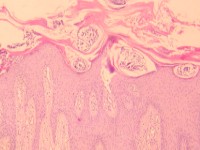

De huidschilfers zitten vol mijten en jongere mijtenstadia. Het volstaat om wat schilfers af te schrapen van een hyperkeratotisch schilferend gebied en daar een KOH-preparaat van te maken, daar moeten dan tientallen mijten en eieren in te zien zijn om de diagnose scabies crustosa te mogen stellen. Deze schilfers zijn zeer besmettelijk. Door het krabben kunnen de met schurftmijt beladen huidschilfers door de kamer dwarrelen en anderen besmetten (verzorgers, medepatiënten, bezoekers, huishoudelijk personeel). Als een patiënt met scabies Norvegica in een instelling verblijft is dat een risico voor het personeel en gelden strengere isolatiemaatregelen. Iedereen die in de kamer geweest is moet preventief worden behandeld met éénmalig ivermectine. Zie ook de richtlijn van het RIVM voor de aanpak van een uitbraak van scabies. In instellingen indien mogelijk de patiënt om de week verplaatsen naar een schone kamer en de oude kamer 1 week niet betreden.

Scabies mijten in het KOH preparaat